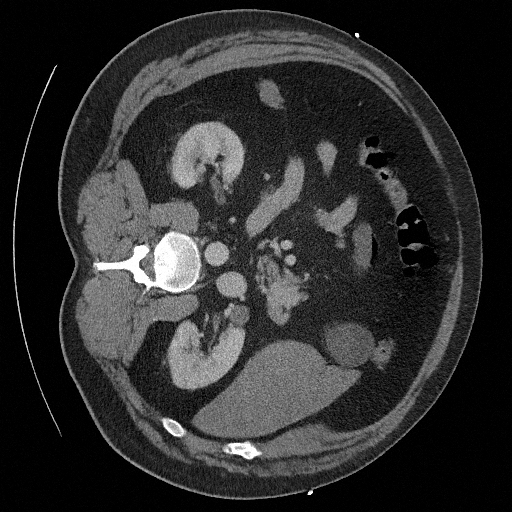

Training a continuous-time score network on Abdomen CT

Hardware: 8 NVIDIA RTX A5000 (24 GB of RAM each)

Sampling results

Original

Perturbed

Samples

Sampled